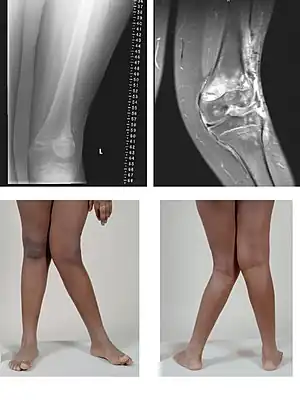

| A very severe case of genu valgum of the left knee following bone cancer treatment | |

Genu valgum, commonly called "knock-knee", is a condition in which the knees angle in and touch each other when the legs are straightened.[1] Individuals with severe valgus deformities are typically unable to touch their feet together while simultaneously straightening the legs. The term originates from the Latin genu, 'knee', and valgus which means "bent outwards", but is also used to describe the distal portion of the knee joint which bends outwards and thus the proximal portion seems to be bent inwards.